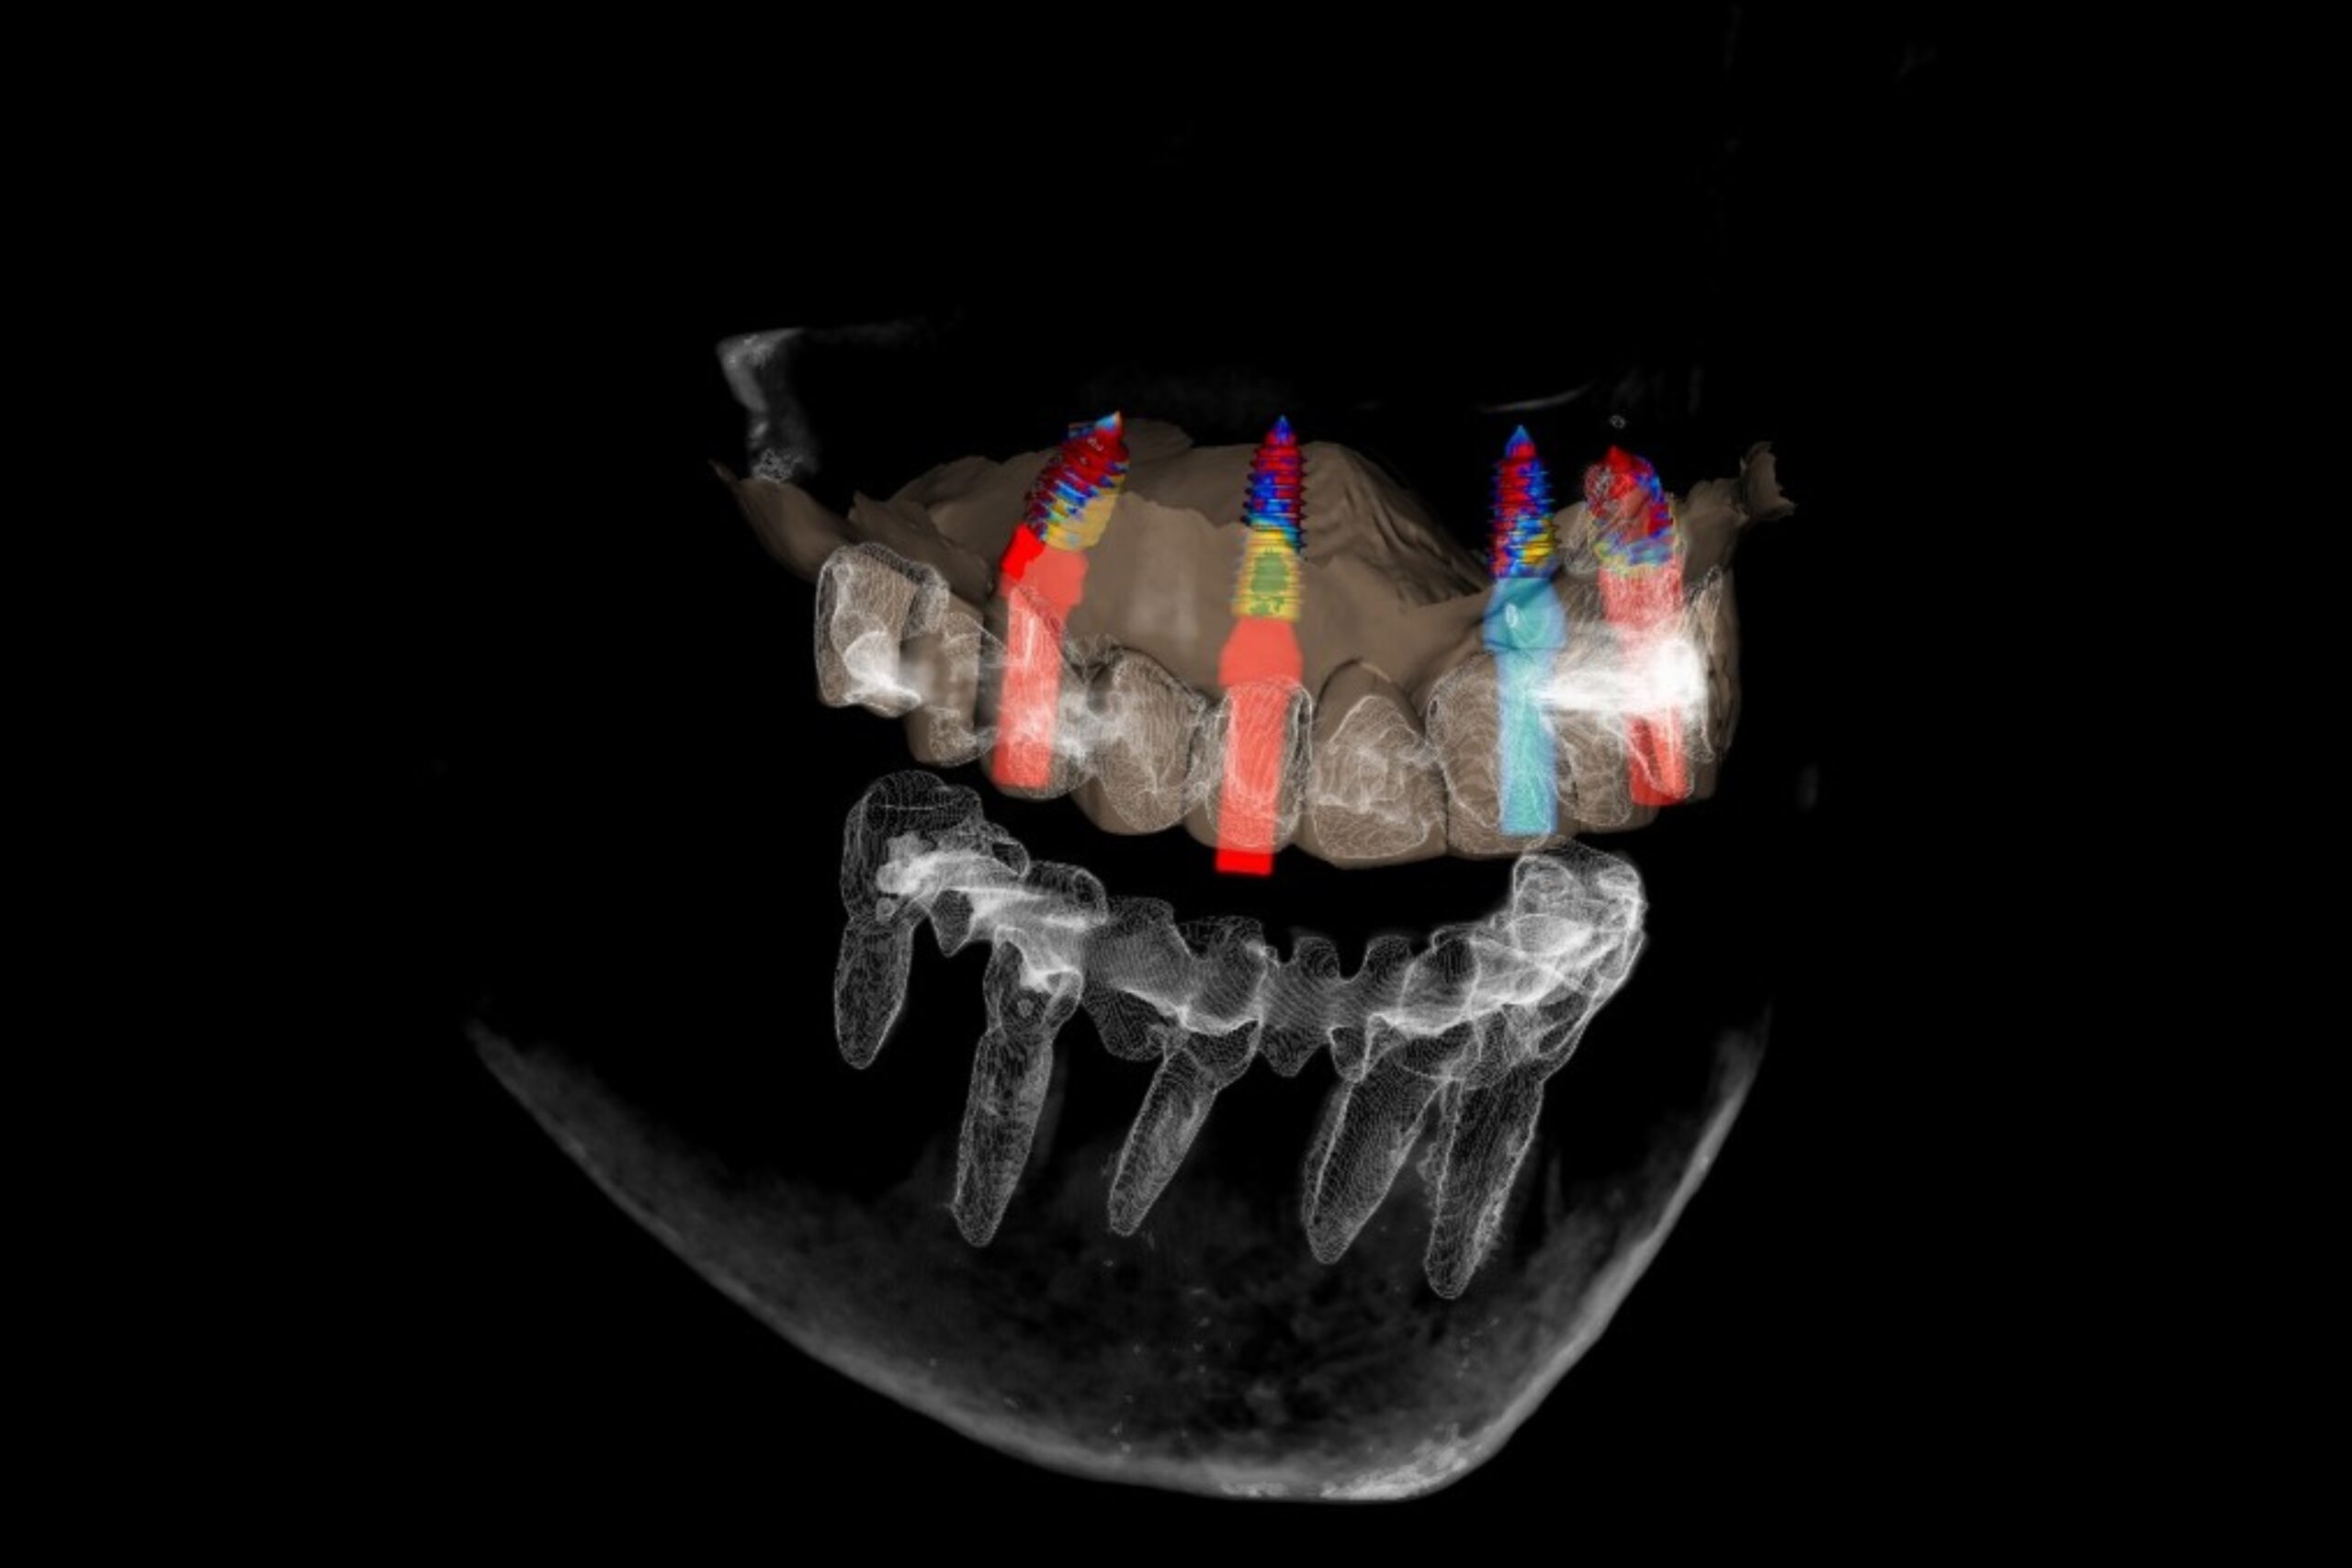

- CBCT (3D CT) felvétel készítése

- digitális tervezés

A digitális tervezés elengedhetetlen, segít a pontos és biztonságos implantátum beültetésben

- az implantátumok típusa és elhelyezkedése

A műtét során négy implantátum kerül az állcsontba. Ez történhet akár azonnali implantációval is, azaz rögtön az eltávolított fogak helyére.

Idönként sebészi sablont alkalmazunk, amelyet előtte digitális megtervezünk ezáltal pontosan az előre megtervezett pozícióba kerülhetnek be az implantátumok. Ez például olyan esetekben fontos, ahol nagyon kevés a rendelkezésre álló csontállomány.

Ezt követően a megfelelő felépítmények csatlakoztatjuk (becsavarjuk) az implantátumokba.